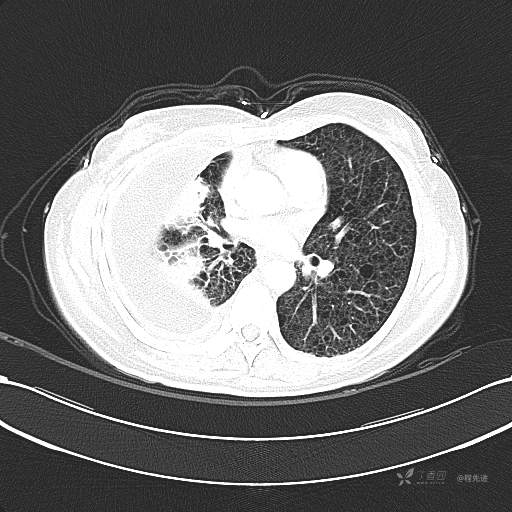

患者性别:女

患者年龄:51岁

简要病史:胸闷半年

肺淋巴管肌瘤病 (7)

乳糜胸 (8)